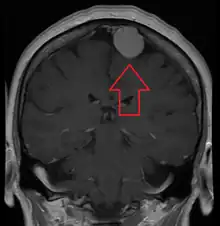

Diagnosis

Meningiomas are visualized readily with contrast CT, MRI with gadolinium,[23] and arteriography, all attributed to the fact that meningiomas are extra-axial and vascularized. CSF protein levels are usually found to be elevated when lumbar puncture is used to obtain spinal fluid. On T1-weighted contrast-enhanced MRI, they may show a typical dural tail sign absent in some rare forms of meningiomas.[18]